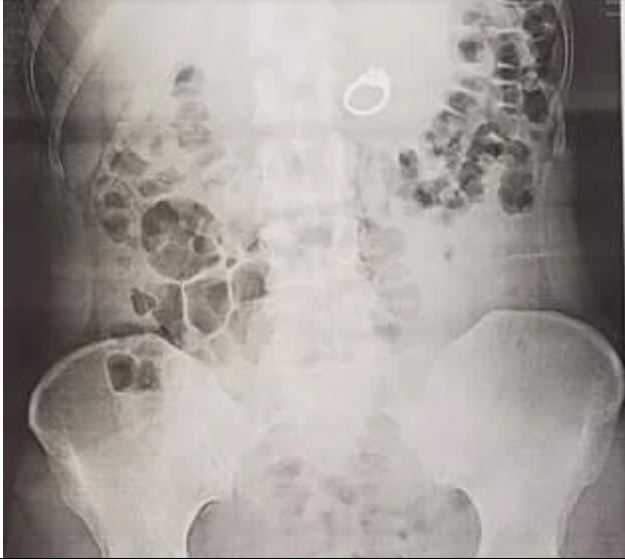

I went to urgent care where I struggled to explain why I was there, because I was laughing/crying so hard. The doctor ordered an Xray and seemed pretty shocked when she walked back in with a second doctor and showed me that sure enough, my ring was right there in my stomach!

So they push the sleepy drugs, and right as I started to feel that wave of warm and fuzzy sleep I said to the doctors, Bobby would LOVE this. Everything went great, they found my ring just beyond my stomach in my intestines, retrieved it and gave it to Bobby, not me.